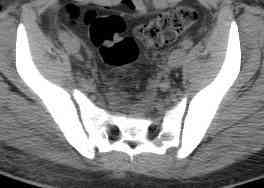

Уважаемые коллеги! опять вопрос по повреждению таза. Больной получил производственную травму 10 дней назад - удар балкой около 3 тонн в область верхней трети правого бедра и лона.

Был диагностирован перелом "типа бабочки" и повреждение уретры. Сделана цистостома. У насв отделении 3 дня. Имеется огромная флюктуирующая гематома с "галифе"-образной деформацией обеих бедер. Пнкционно эвакуировали в несколько приемов из подфасциальных полостей на бедрах около 3 литров геморрагического отделяемого с последующей эластической компрессией. При пункциях выявлено сообщение полостей на бедрах - видимо через поравннуюдиафрагму дна и полость таза - при удалении крови справа уменьшался объем левого бедра. Какой то активности проявялять покабоимся - аппаратная фиксация через отслоенные ткани представляется чреватой нагноением, открытая фиксация в условиях такой гематомы тоже не радует. Хотелось бы услышать ваше мнение

С моей точки зрения, бояться аппарата внешней фиксации не надо. Более того, он абсолютно показан, и чем раньше, тем лучше.

Явная ошибка - прекратите мучить пациента и выполните дренирование по Буяльскому-Мак-Уортеру. Судя про всему - возможно неполноценное дренирование мочевого пузыря, и то, что вы принимаете за гематому, на самом деле является урогематомой. Бойтесь флегмоны внутритазового пространства!!

18.12. - отдельное спасибо еще раз А.В.Рункову- больного оперировали (А.В.Рунков) - произведен остеосинтез аппаратом - фиксация за крылья, два стержня в лонные кости и репозиция (почти полная) снимки будут чуть позже.

Дренировали отслойки на бедрах с их санацией. В правой ягодичной области сформировалась зона некроза. Больной "подвешен" за аппарат.